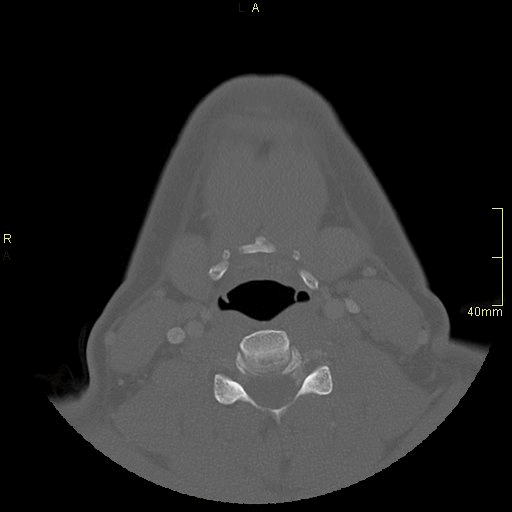

CT Facial Bones/Sinuses Contrast- Bone window (axial)